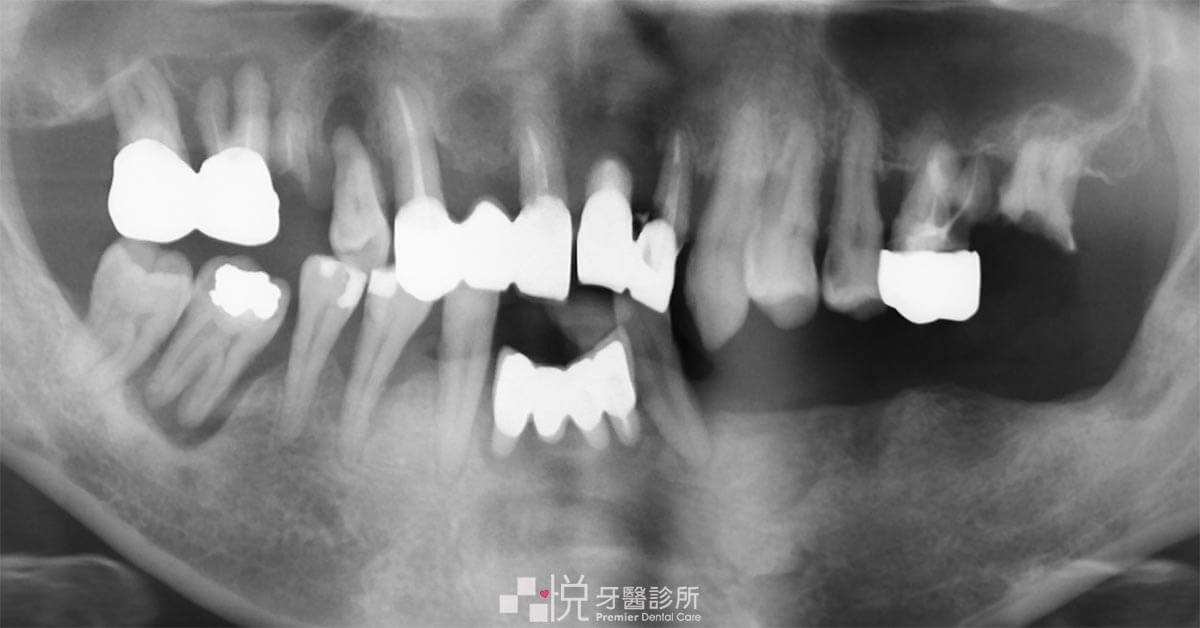

陳媽媽牙周病的牙齒,有幾顆因為不斷腫痛不得已早就拔除,但因為害怕看牙,所以一直沒有處理。活動假牙不好用,也是有一搭沒一搭的在使用。

慢慢的齒列就產生了歪斜,然後牙齒不只搖晃,咬合空間的喪失也產生了明顯的爆牙。

因為長期缺牙、多顆缺牙、牙齦骨質不夠對於植牙的難度都倍增,傳統的治療時間上也常需要一兩年才能完成,而且多次的手術,術後的不適及腫痛都是一次又一次的挑戰。

因為 All-on-4 手術需要把全顎無法挽救的牙齒拔除,所以植牙時的參考點會變得很少也很難掌握植牙的位置和角度。

若手術搭配 3D 藍光 X-Guide 導航植牙機,就可以利用最新的定位技術,無時差的即時回饋讓植牙手術醫師可以完全掌握植入過程中的動態,把可利用的骨脊條件作最佳的利用,達成植體穩定度的最大化。也可以把植體的角度準精植入,讓後續假牙製作可以更順利,也讓假牙的強度可以因良好的植入位置而確保堅固!